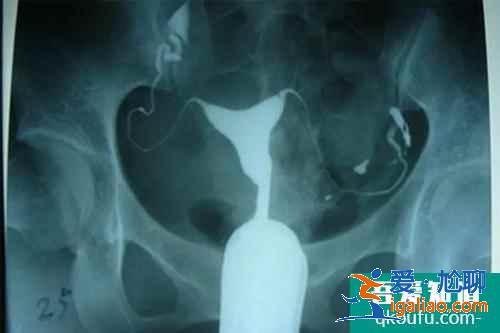

輸卵管造影術?

女性不孕中,輸卵管因素導致的不孕占據約三分之一,在繼發性不孕的人群中所占的比例更大。所以,醫生會建議做子宮輸卵管造影檢查,好多女性朋友對于輸卵管造影有很多困惑,下面就談談關于輸卵管造影的幾個常見問題。...